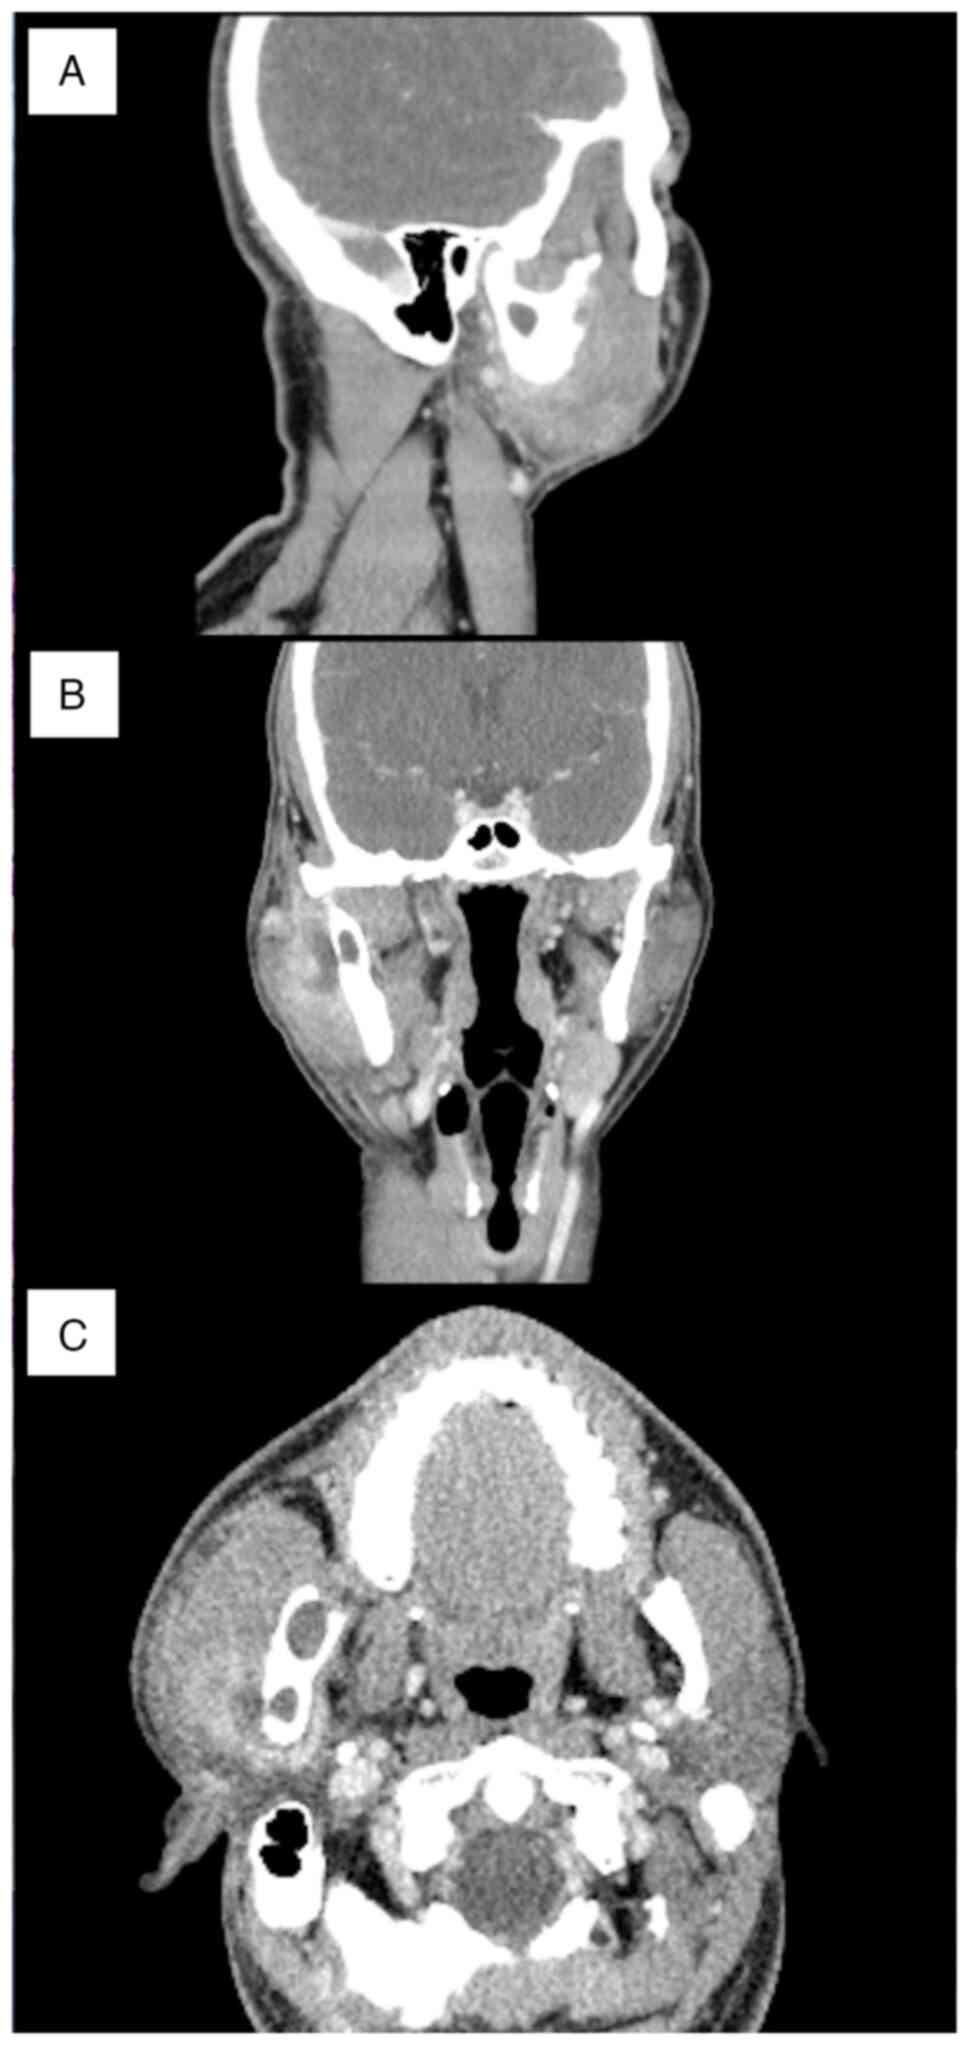

the General Anesthesia Department, symptoms of swelling and pain

occurred around the condylar process in December 2020. A contrast

computed tomography examination showed the formation of an abscess

at the cyst at the base of the condyle. Swelling of the surrounding

tissues, including the parotid gland, was also observed (Fig. 5A-C). Anti-inflammatory treatment

included incision, drainage and antibiotics.